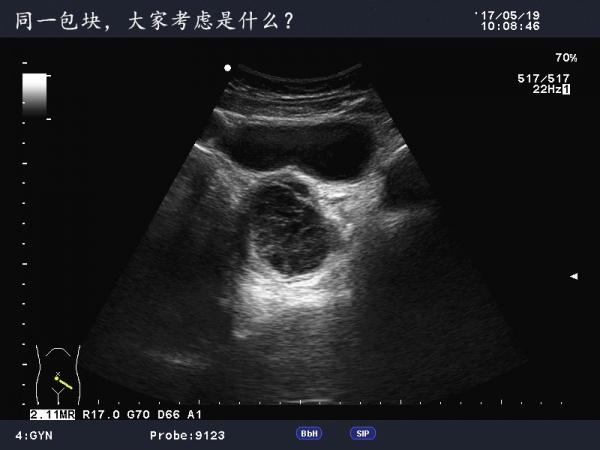

这是巧克力囊肿吗?

患者女,40Y,因下腹部疼痛就诊,最近一次月经来潮量少且疼痛厉害,以往基本上正常。

于月经第11天行B超检查。

不是很典型的巧克力囊肿,可以随访复查看看

可定期复查,黄体不除外